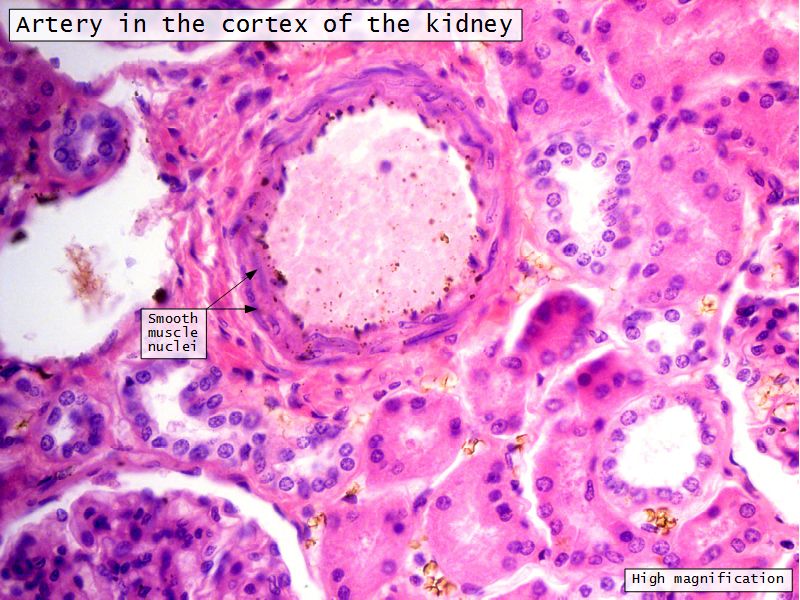

Blood flow

- Efferent arteriole

- Smooth muscle in media

- Capillaries

- Fenestrated

- Afferent arteriole

- Smooth muscle in media